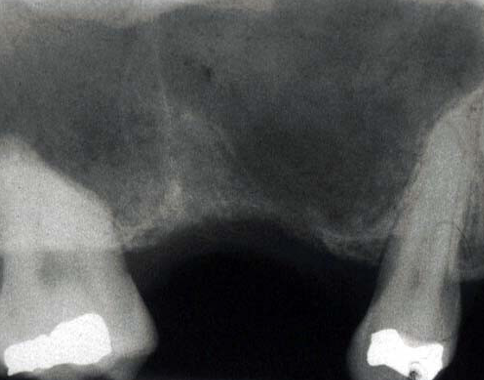

how can you tell this is oaf

less bone there where communication happened